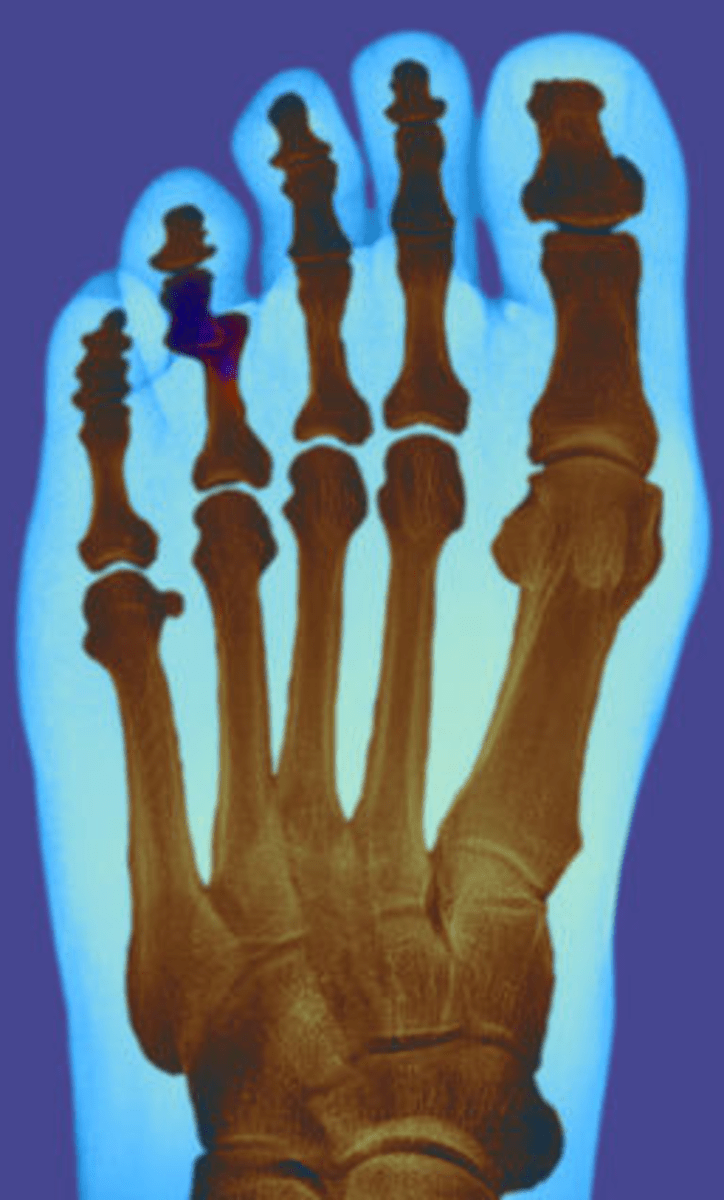

gout symptoms big toe What Does Shooting Pain In Toes Mean Toe pain can result from a variety of causes, including osteoarthritis, gout, turf toe, bunions, ingrown toenails, fractures, sesamoiditis, dactylitis, claw and hammer toes,. Toe pain is any uncomfortable sensation in the toes. Conditions that can cause big toe pain include arthritis, gout, and. There are many things that can cause sharp pain in the toes. Pain in the big. What Does Shooting Pain In Toes Mean.

Symptoms You Have a Broken Pinky Toe or Stubbed Toe, Difference in What Does Shooting Pain In Toes Mean Pain in the big toe can indicate an injury or an underlying health condition. Pinched nerves, tendinitis, fractures, tumors, and medication are some of the most common reasons why you can. It may be a little irritating or so debilitating that you cannot put any kind of. There are many things that can cause sharp pain in the toes. Toe. What Does Shooting Pain In Toes Mean.